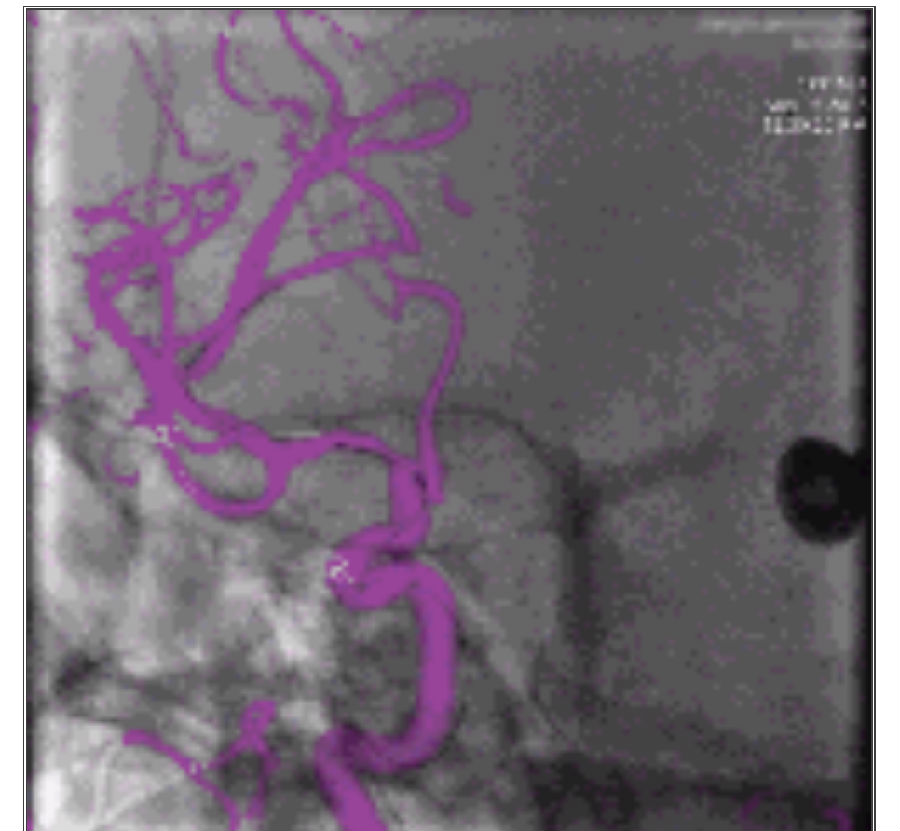

影像融合技术在脑脊髓血管病中探索及创新